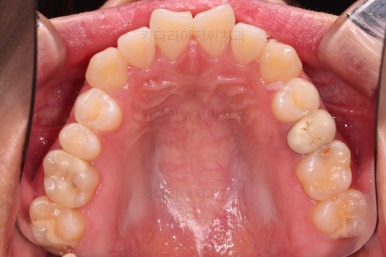

1. 처음 내원 시의 입안의 모습

부산치아교정잘하는곳 키다리아저씨치과에 처음 내원하셨을 당시의 입안 모습입니다.

얼핏 보면 많이 삐뚤어지지는 않은 편인데, 눈에 바로 띄는 앞니가 뻗쳐 있으면서 획 돌아있는데요. 정렬이 필요한 상황이었습니다.

어금니쪽은 많이 삐뚠 편은 아니었으며, 윗니 앞니가 많이 앞으로 뻗쳐 있는 상태였습니다.